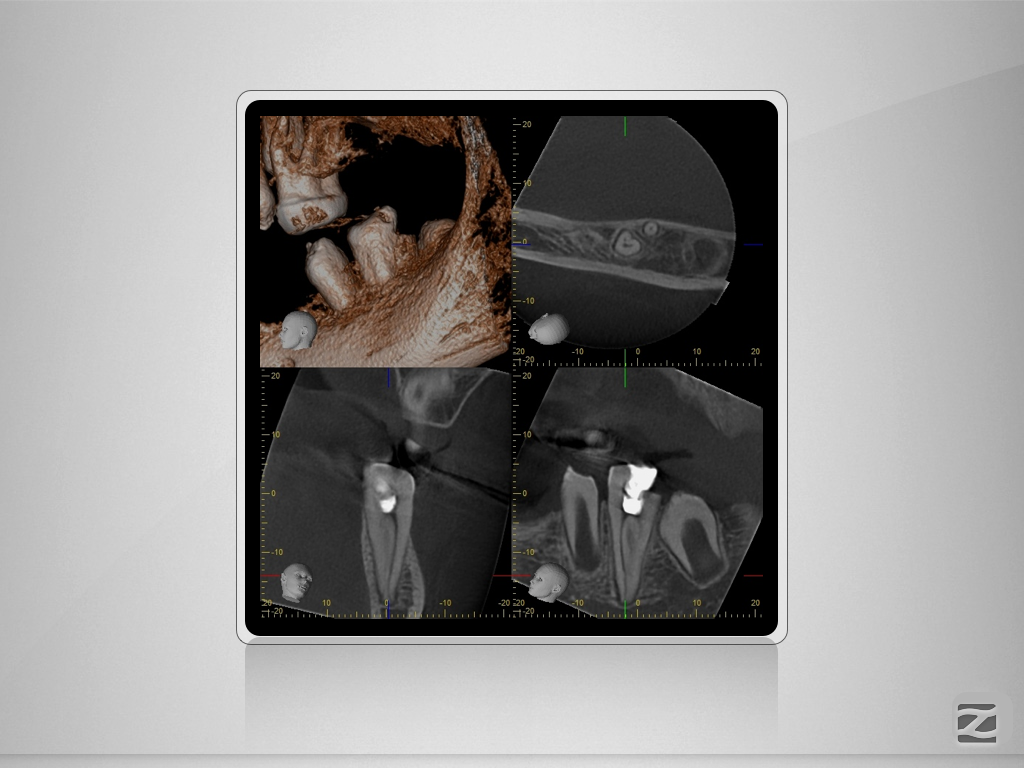

36D.005

Wie wäre es ohne DVT?